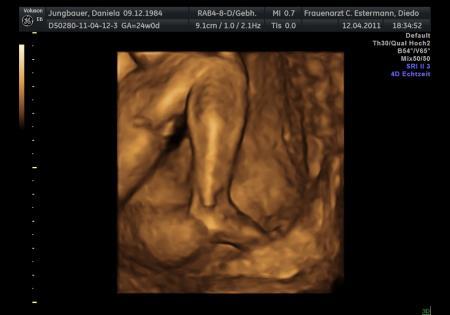

Und von der Seite beim Fruchtwasser schlürfen!

Bild zu